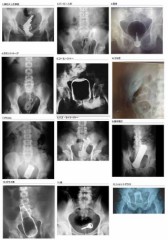

顔も名前も公開されないにせよ、画像の様に症例として残されたら嫌だろうね